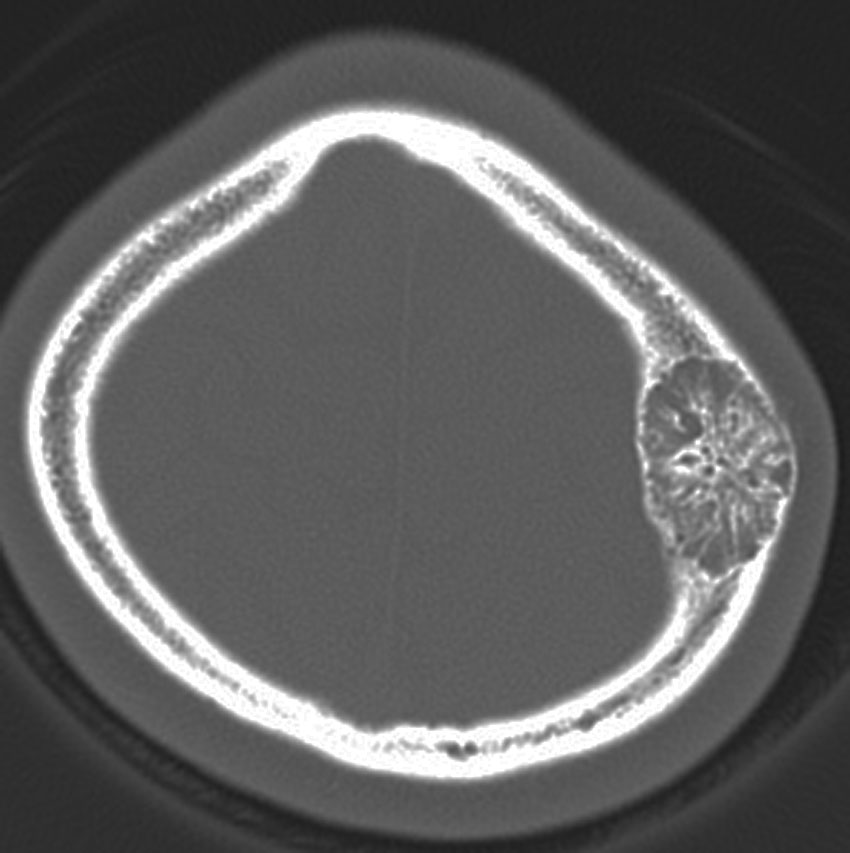

朝倉書店『内科学』(第12版)デジタル付録, 頭蓋骨腫瘍 skull tumor | 脳外科医 澤村豊のホームページ,

頭蓋骨腫瘍 skull tumor | 脳外科医 澤村豊のホームページ,[A11078202]リハビリテーションプログラムの手引書―身体障害の評価のために [単行本] B.C.ABREU; 矢崎 潔